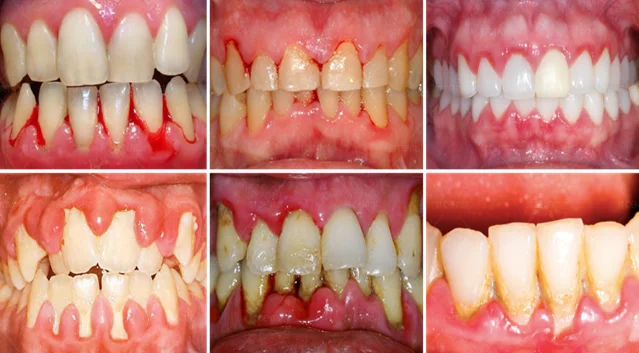

Bệnh nha chu đôi khi tiến triển mà không có các triệu chứng đáng chú ý, nhưng bạn có thể nhận thấy một hoặc một vài triệu chứng sau:

- Nướu răng sưng hoặc tấy đỏ

- Chảy máu chân răng khi bạn chải răng hoặc nhai thức ăn cứng

- Nướu trở nên nhạy cảm

- Mô nướu bị tụt

- Có mủ ở đường viền nướu

- Hôi miệng hoặc đắng miệng

- Răng bị thưa do lung lay.

Các giai đoạn của bệnh viêm nha chu

Viêm nha chu xuất hiện và tiến triển theo 4 giai đoạn:

- Giai đoạn 1: Vôi răng hình thành do các mảng bám lâu ngày khiến vi khuẩn tích tụ ở cổ răng, kẽ răng gây viêm nướu

- Giai đoạn 2: Viêm nướu gây sưng phù, chảy máu lợi, có giảm giác nhức

- Giai đoạn 3: Viêm nướu trở nặng thành viêm nha chu, hình thành những ổ viêm nhiễm có mủ

- Giai đoạn 4: Viêm nha chu nặng, phá hủy xương răng, gây tụt lợi. Khi đó răng không còn được nướu bao bọc, dễ bị lung lay và người bệnh có nguy cơ rụng răng